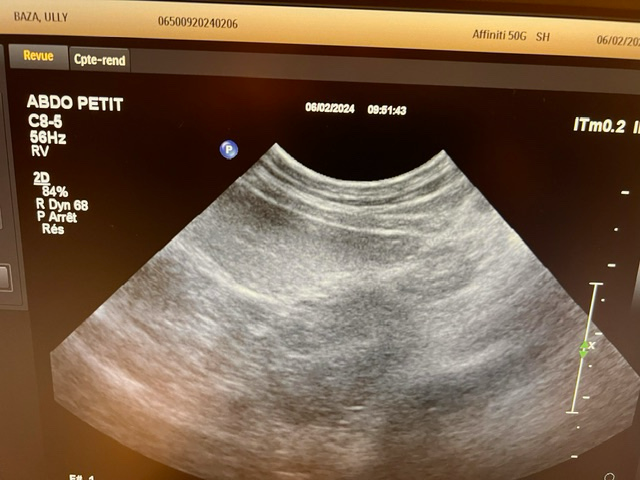

강아지가 목줄을 하고 산책 중에 갑자기 집에 가려고 차도로 뛰어드는바람에 교통사고가 났습니다. 천천히 달려오는 차에 부딪히기는 했지만 걱정돼서 바로 병원으로 갔고 엑스레이, 초음파, 혈액검사 다 시행했지만 이상이 없다고 얘기했습니다. 그런데 사고 이후로 계속 토를 해서 병원에 가서 구토약이랑 진통제를 받아와서 먹였는데도 계속 구토를 하네요ㅠ 사료를 그대로 토하는데 이게 스트레스때문인지 아니면 검사상에 이상이 있는지 여쭤보고 싶어서 글 남깁니다. 또한 가슴쪽을 부딪혔는데 흉부 엑스레이 상에서 이상소견이 있는지 확인 좀 부탁드립니다.

초음파 검사의 경우 초음파를 직접 본 사람이 아니면 찍어놓은 사진으로는 아무런 판단을 할 수 없고 해서도 안됩니다.

주치의의 판단이 가장 정확한 판단이겠으나 지현형으로 장기 손상이 일어나는 경우가 종종 있기 때문에 증상이 지속된다면 복부 초음파 검사를 다시 받아볼 필요가 있어 보입니다.